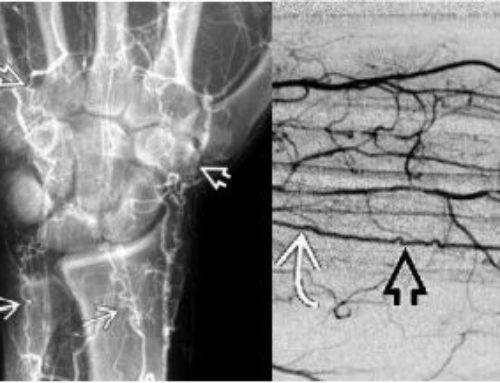

- Diminished or Absent Pulse: A key indicator, often in the wrist (radial pulse), leading to the name “pulseless disease.”

- Imaging Findings: MRI, CT, or ultrasound scans showing thickening and inflammation of the aorta and its major branches.